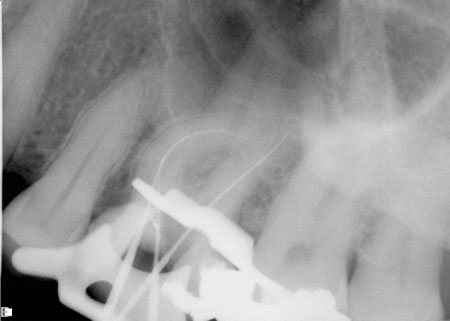

In the following case, the author used several of the above suggestions to properly determine working length. This tooth was diagnosed with irreversible pulpitis, and multiple visits were required to complete the case. While the maxillary sinus and zygoma often interfered in the author’s interpretation of the tooth’s anatomy, the tooth’s anatomy itself proved to be the largest obstacle to performing ideal root canal therapy (Figure 1). Originally, a periapical radiograph was taken to determine if the mesial canals actually curved as severely as the hand files had indicated. A periapical radiograph was then taken to approximate the measurements (Figure 2). Just from his own tactile sensation, the author came close to approximating the proper length of the canals but was not entirely accurate.

Figure 1 Preoperative radiograph demonstrating complex anatomy.

Figure 2 An approximate working-length radiograph.

Using the Foramatron, a length measurement was taken to determine precise working length. This apex locator is particularly easy to use because its display allows for good visibility of when canal length has been properly achieved. It is also straightforward, accurate and technique-friendly for both the advanced clinician as well as those using an apex locator for the first time.

For accuracy purposes, a digital periapical radiograph was taken to confirm the measurements (Figure 3). Notice that although the tooth had four canals, which is highly common for maxillary first molars, files were not placed in all four of them. Placing files in all four canals can sometimes impede a clinician’s ability to accurately visualize where a canal ends. In order to see all four canals it is more effective to take another digital radiograph to get an accurate measurement rather than take several poorly angled views.

Figure 3 Radiograph confirming lengths determined by apex locator.